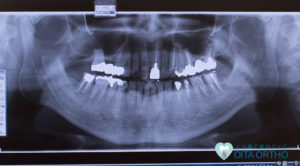

歯は「歯根部」と言われる歯ぐきに埋まっている部分と、「歯冠部」と言われる歯ぐきから出ている部分に分けられます。差し歯とは基本的に「歯冠部」に被せ物をした歯のことを指し、矯正歯科治療は、歯の根もとから動かしていく治療なため、被せ物の部位や大きさにもよりますが、歯根部がしっかりしていれば、差し歯があっても、たいていの場合は問題なく矯正治療をすることができます。

しかし、何本か歯を失っていて、大きなブリッジが入っている場合には、ブリッジを一度外して、プラスチックで作られた仮歯などの人工歯を入れてから治療するケースもあります。

今回の「差し歯があっても矯正歯科治療は可能か」というテーマについては、「歯根部がしっかりしていれば矯正治療はたいていの場合可能」という結論でしたが、歯列矯正は治療を始める前に歯や歯茎の状態などをよく調べた上で、矯正治療が可能かどうかを判断します。

また、歯をどこに動かすのか、あるいは歯を抜いてある隙間はどうするのか、今入っている詰め物や被せ物はどうするのか等を検討し判断します。歯を健康的に保つためには、無理に矯正治療だけで解決するというよりも歯周治療・補綴治療などを含めた診断をすることが非常に大切になってきます。